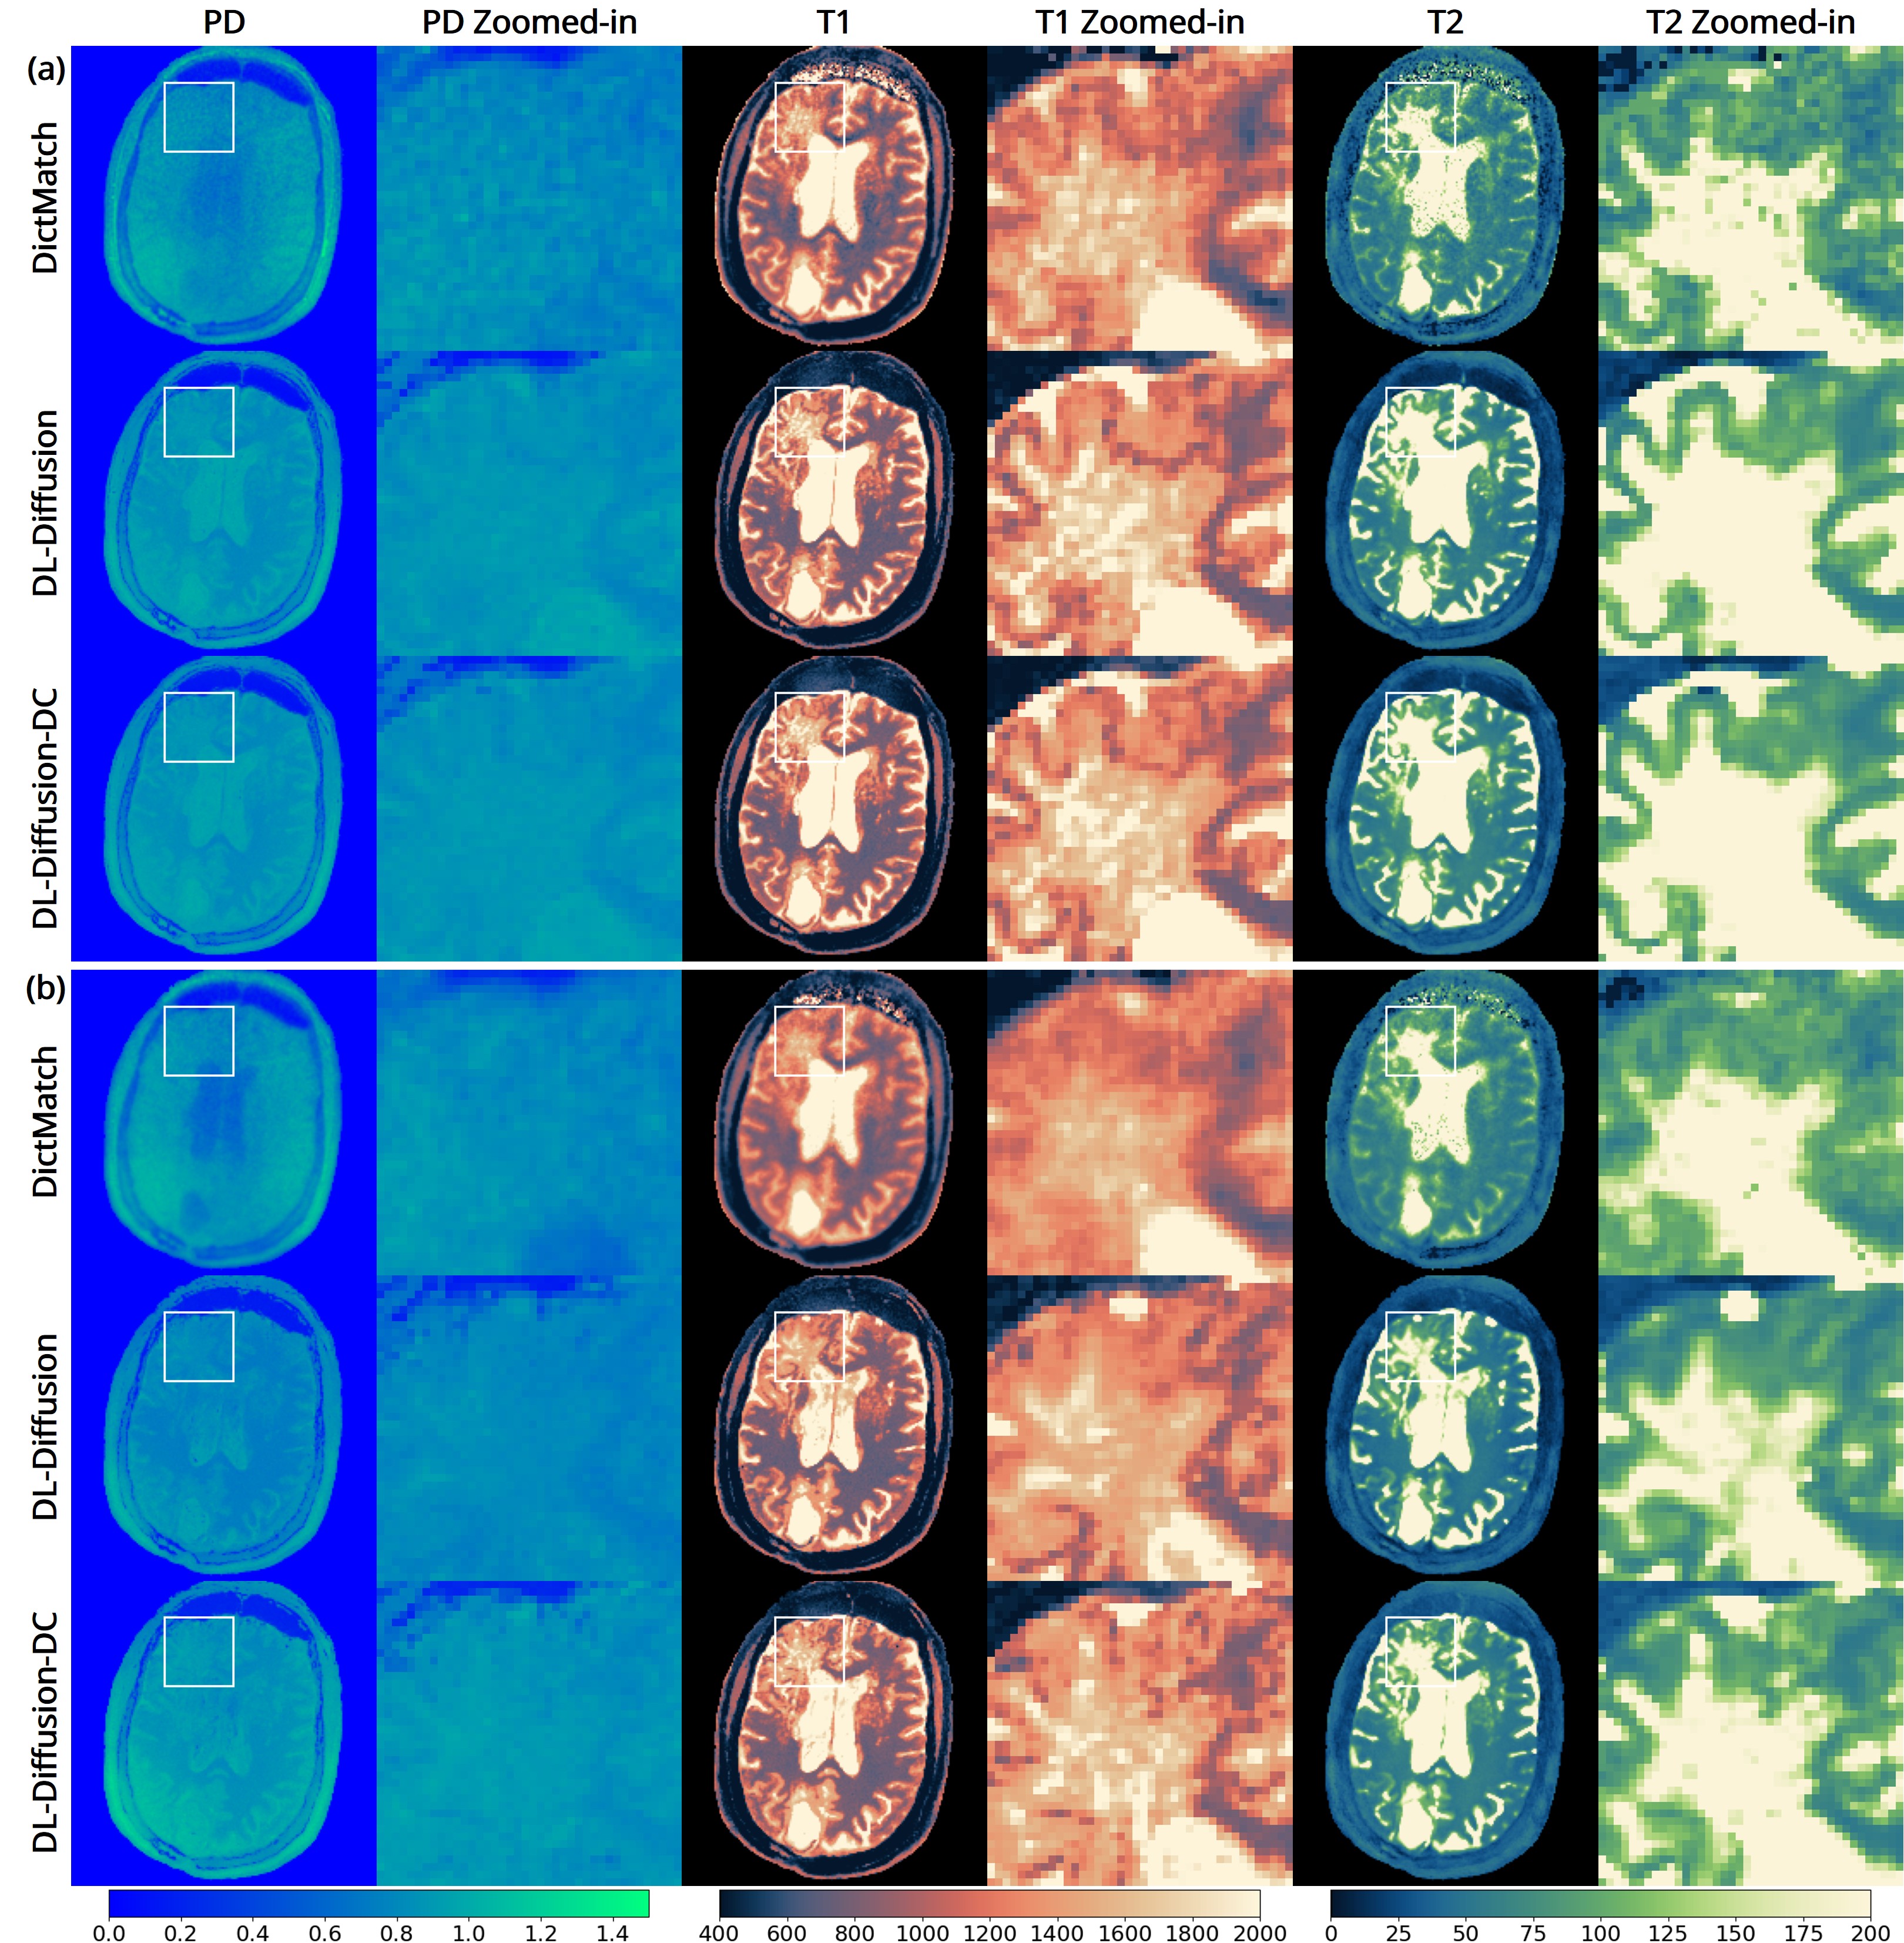

The 3D fast silent multi-parametric mapping sequence with zero echo time (MuPa-ZTE) is a novel quantitative MRI (qMRI) acquisition that enables nearly silent scanning by using a 3D phyllotaxis sampling scheme. MuPa-ZTE improves patient comfort and motion robustness, and generates quantitative maps of T1, T2, and proton density using the acquired weighted image series. In this work, we propose a diffusion model-based qMRI mapping method that leverages both a deep generative model and physics-based data consistency to further improve the mapping performance. Furthermore, our method enables additional acquisition acceleration, allowing high-quality qMRI mapping from a fourfold-accelerated MuPa-ZTE scan (approximately 1 minute). Specifically, we trained a denoising diffusion probabilistic model (DDPM) to map MuPa-ZTE image series to qMRI maps, and we incorporated the MuPa-ZTE forward signal model as an explicit data consistency (DC) constraint during inference. We compared our mapping method against a baseline dictionary matching approach and a purely data-driven diffusion model. The diffusion models were trained entirely on synthetic data generated from digital brain phantoms, eliminating the need for large real-scan datasets. We evaluated on synthetic data, a NISM/ISMRM phantom, healthy volunteers, and a patient with brain metastases. The results demonstrated that our method produces 3D qMRI maps with high accuracy, reduced noise and better preservation of structural details. Notably, it generalised well to real scans despite training on synthetic data alone. The combination of the MuPa-ZTE acquisition and our physics-informed diffusion model is termed q3-MuPa, a quick, quiet, and quantitative multi-parametric mapping framework, and our findings highlight its strong clinical potential.💡 Summary & Analysis